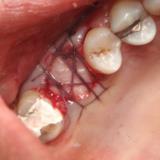

Immediate Implant Placement

A molar either maxillary or mandible always represents a little difficult and tricky scenario for implant placement immediately after extarction. There is always some sacrifice for the location, angle etc. however you save some time and patients go through a procedure once and it is a reliable method of replacing a tooth, when feasible. Dental implant is always a compromised replacement and a tooth restored with immediate placement is not any different.